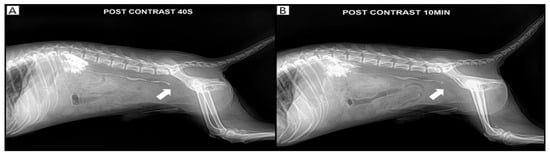

Antegrade pyelography was performed following percutaneous ultrasound-guided pyelocentesis under butorphanol sedation (Butophan Inj.®, Myungmoon Pharm. Co., Seoul, Republic of Korea; 0.2 mg/kg, intravenously), with aseptic skin preparation, to evaluate for other potential causes of ureteral obstruction, such as an ectopic ureter or ureteral stricture. Using a 23-gauge needle, 2 mL of urine was aspirated from the renal pelvis, followed by antegrade intrapelvic injection of 1 mL of iohexol (300 mg iodine/mL; Omnipaque® 300, GE Healthcare Co., Ltd., Shanghai, China) [11]. Abdominal radiographs were subsequently obtained after patient repositioning. Persistent contrast retention at 10 min confirmed ureteral obstruction (Figure 3).

Figure 3. Pyelography confirmed the right ureteral obstruction (white arrow). Contrast agent retention of the kidney and ureter was observed after 10 min of contrast on day 4. (A): 40 s post-contrast pyelography, (B): 10 min post-contrast pyelography.